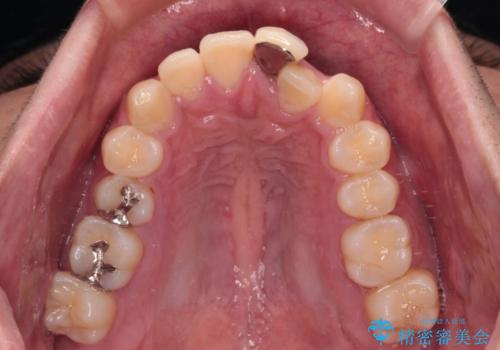

上下ともに歯列幅が狭く、その影響でデコボコになっていたため、ワイヤー装置を用いて歯列を側方に拡大しながら、デコボコを解消していくこととしました。

矯正治療後には気になっていた前歯をセラミッククラウンにし、自然な口元に仕上げることができました。